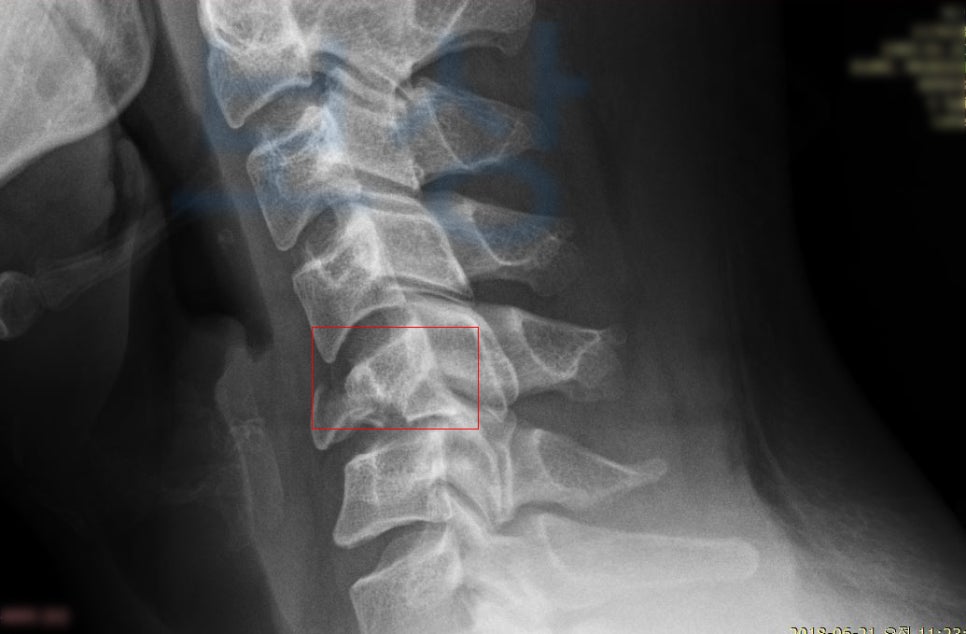

박@@님은 새벽 운전 중 차량이 미끄러지며 전복되는 사고를 당하셨습니다.

이 사고로 급하게 응급실 내원하여 정밀 검사를 실시하셨는데요,

경추골절 s12.9

을 주 진단으로 받게 되었고 흉추의 골절 s22.0 도 함께 진단받았죠. 최소 12주간의 요양이 필요했고 앞으로의 생활 또한 어떻게 변화될지 모르는 상황이었습니다. 먼저, 후유 장해 보상은